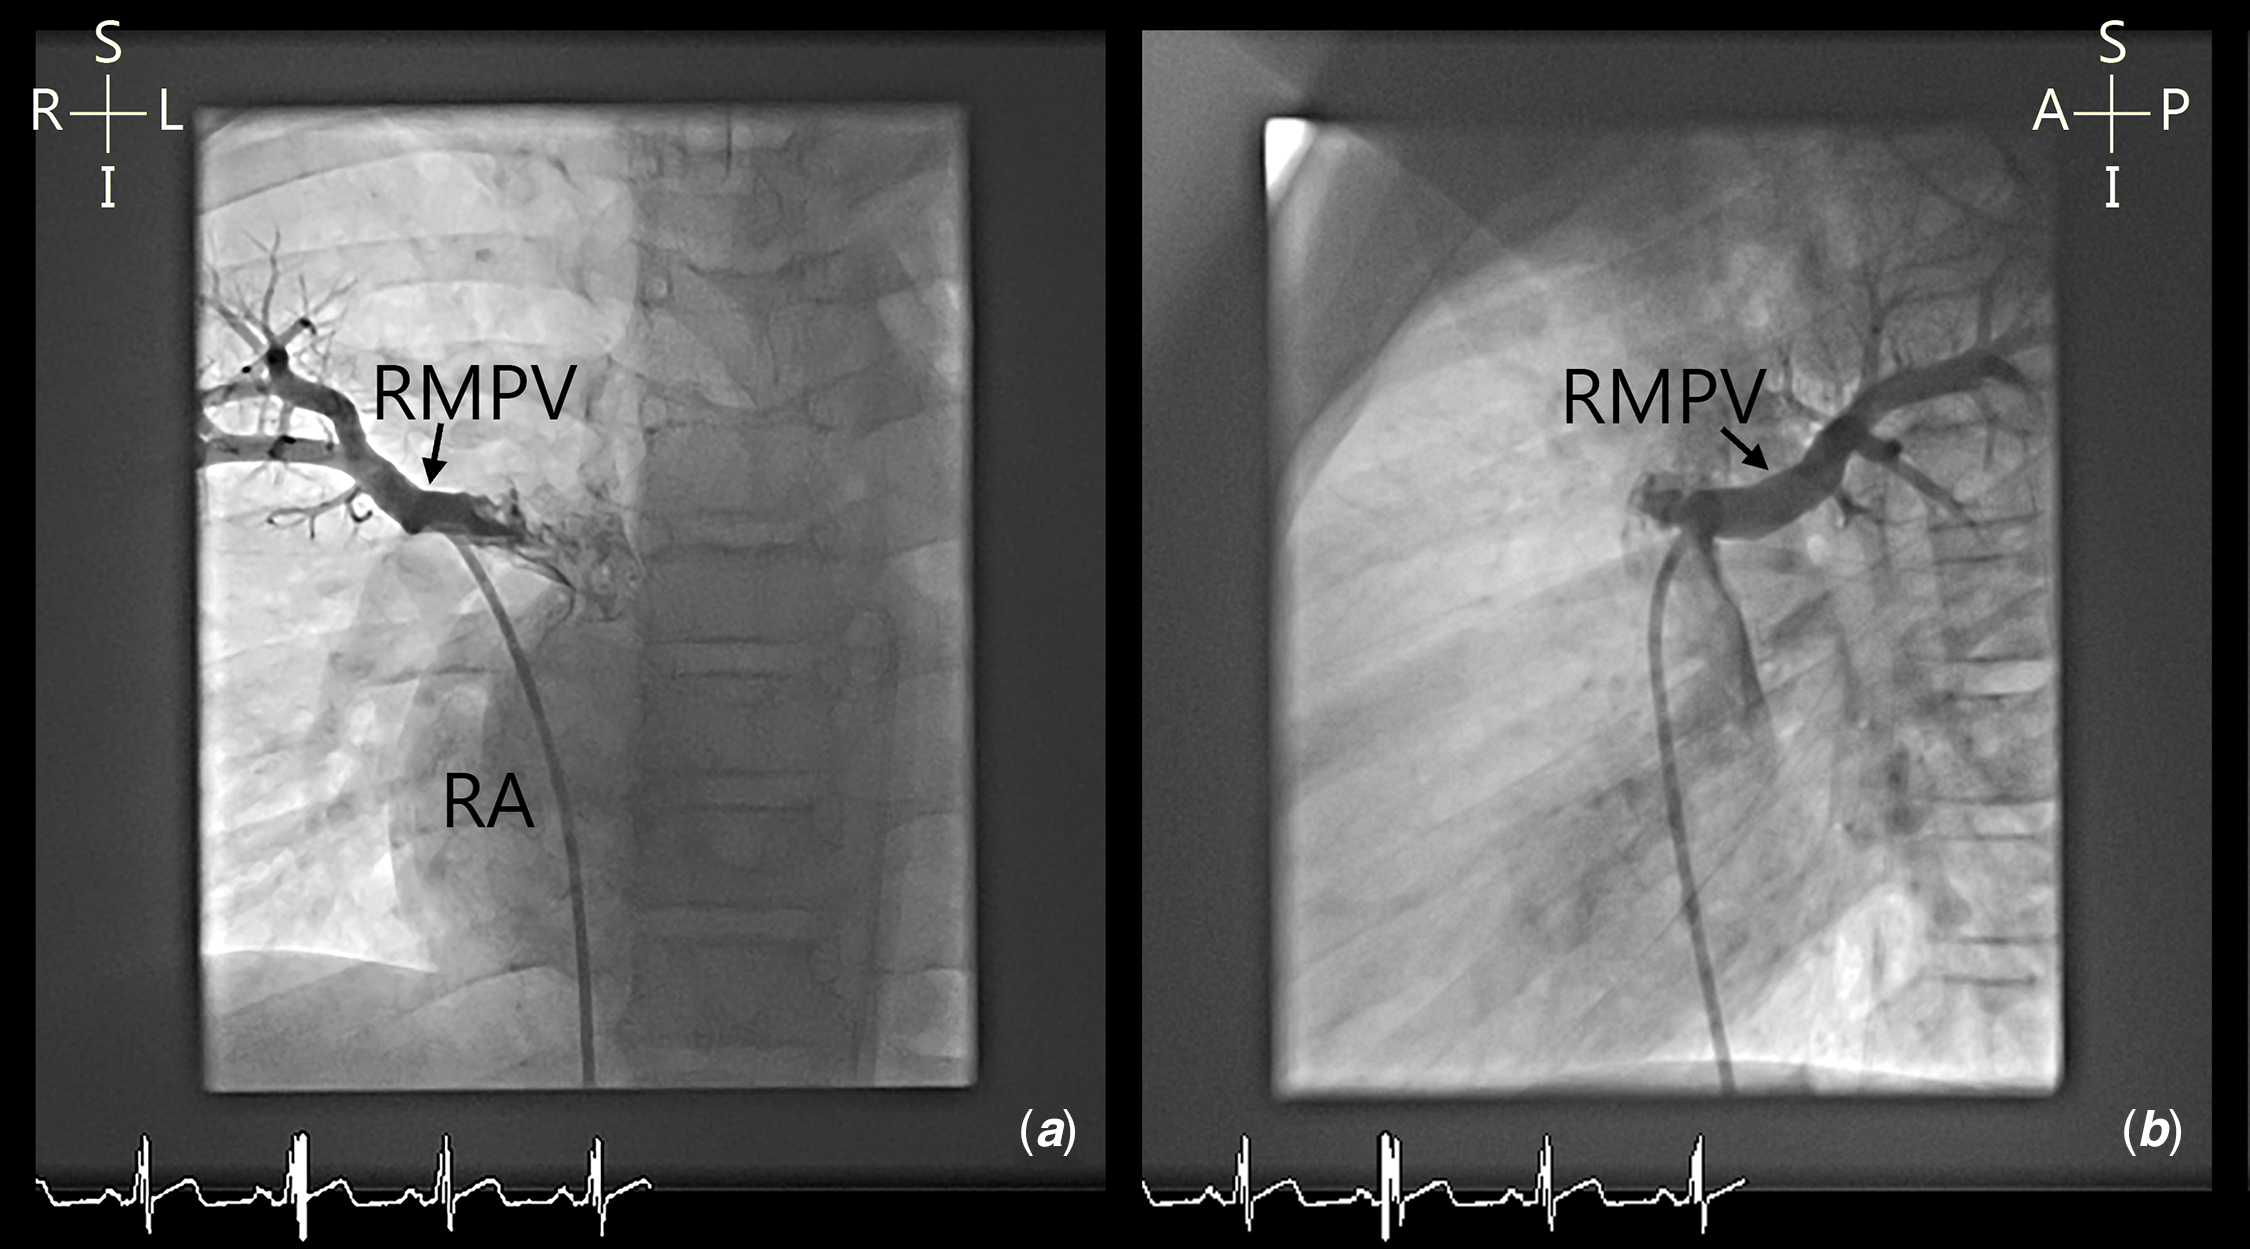

Five patients had complex pulmonary venous variants. Four patients had high insertion of anomalous vein into the superior caval vein (Fig 4) and three patients had multiple anomalous veins draining to different sites, two of whom had high drainage of one vein to the superior caval vein (Fig 5). Six of the 37 patients have bilateral superior caval veins.

Figure 4. ( a and b ) Cardiac angiography demonstrating anomalous right middle pulmonary vein (RMPV) into right superior caval vein/right atrium junction. RA=right atrium.